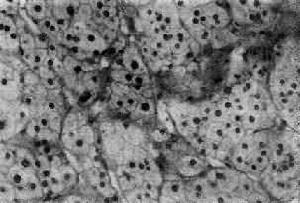

Ⅰ型發病機制病理:假性醛固酮減少症可分為Ⅰ型與Ⅱ型,其中Ⅰ型呈常染色體隱性遺傳者,基因突變使集合管上皮細胞鈉通道蛋白亞單位功能喪失,鈉再吸收功能障礙。腎小管細胞對內源性醛固酮反應性減低,腎小球及其他腎小管功能正常。常色體顯性遺傳者為鹽皮質類固醇受體功能障礙Ⅱ型,發病機制不明。Ⅰ型發病機制如圖。